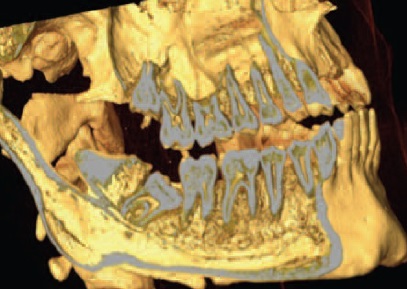

Наиболее часто альвеолит возникает после удаления зубов нижней челюсти, особенно третьих моляров с затрудненным прорезыванием, при котором происходит значительная травма мягких тканей и кости челюсти. Так, на рис. 3 и 4 представлены клинические случаи затрудненного прорезывания аномально расположенных зубов 48. Особенности расположения зуба 48 и его соотношения с зубом 47 позволяют предположить с высокой долей уверенности, что удаление зуба 48 будет очень травматичным.

Рис. 3. Компьютерная томограмма челюстей. Аномалия положения зуба 48.